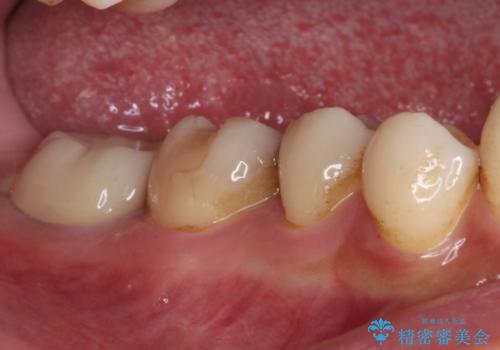

- かかりつけ医にて、歯の高さが不足しているためセラミッククラウンの装着はできないと言われたとのことで来院された患者様です。

診察したところ、確かに歯の高さは不足していましたが、土台の立て直しや歯の削り方を調整することでオールセラミッククラウンでも補綴可能と思われました。

ただし、クラウンの厚みは極力薄くした方が維持力が増すため、高強度のフルジルコニアクラウンにて補綴治療することとしました。

仮歯が途中外れることもなく、無事に補綴治療を行うことができました。

歯石や磨き残しなどが多いため、今後クリーニングを行っていきます。